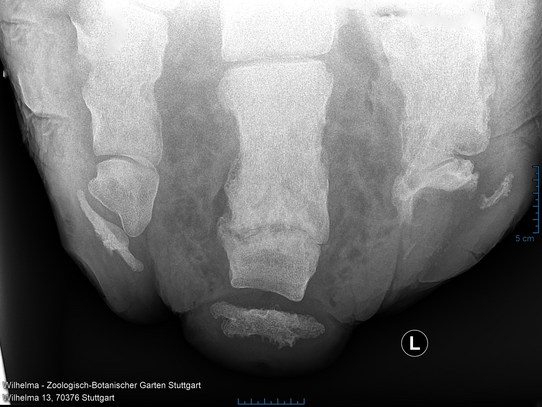

Case 1: Asian elephant

The elephants at Wilhelma undergo a comprehensive health check every year. The elephant cow Pama (born in 1966) has had a chronic hoof abscess for decades, which is checked annually by X-ray images of the hooves.

Thanks to intensive therapy measures with daily foot care, the inflammation has been well controlled. Fortunately, this year's images showed no progression of the disease – a positive sign for the effectiveness of the treatment.